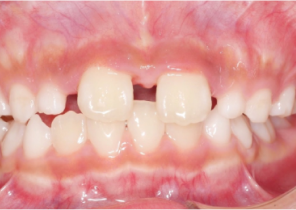

Przed ekspansją eInvisalign Palatal Expander

Po ekspansji Invisalign Palatal Expander

Po leczeniu Invisalign First

Opis przypadku nr 2

7 lat, 11 miesięcy, 24 etapy leczenia Invisalign® Palatal Expanders

Dzięki uprzejmości dr. Davida R. Boschkena

Po leczenie Invisalign Palatal Expander